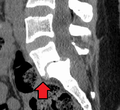

Spondylolisthesis L5/S1

Spondylolisthesis L5/S1 Spondylolisthesis L5/S1

Spondylolisthesis L5/S1 Spondylolisthesis L5/S1. Blue arrow normal pars interarticularis. Red arrow is a break in pars interarticularis

Spondylolisthesis L5/S1. Blue arrow normal pars interarticularis. Red arrow is a break in pars interarticularis Spondylolisthesis L5/S1

Spondylolisthesis L5/S1